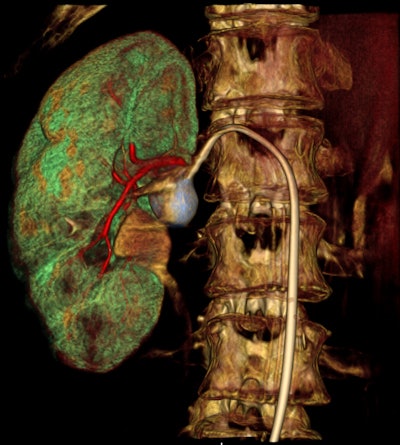

As interventional procedures become more complex, advanced 3D acquisition is becoming increasingly important, he pointed out. There is also an emphasis on flexible, responsive technology, so the C-arm's lateral movement allows it to be moved out of the way during a procedure. During lung biopsies, for example, the unit can be flipped through 180ï‚° to place the flat-panel detector beneath the patient table.

The machine can record static, dynamic, and real-time 3D sequences, and the full range of its potential applications is still to be explored. But there are clinical applications in which it already appears to have advantages over CT, notably in investigations of upper limb fractures in obese patients and weight-bearing lower-limb bone examinations of diabetics, he added.